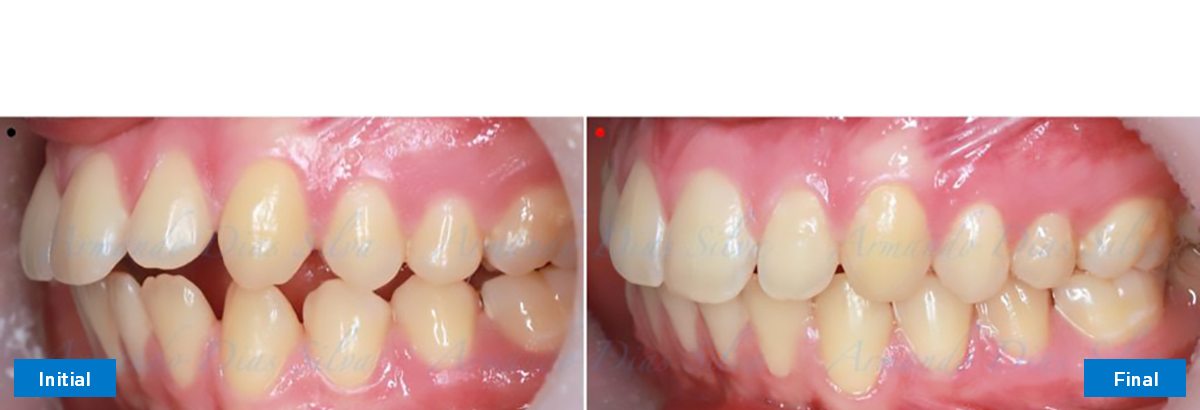

Modalidades: Software y SureSmile® Aligners

Duración: 7 meses, 7 citas

N.º de alineadores -Superior: 24 Inferior: 16

Se logran todos los objetivos principales:

• Molares de clase I logrados con distalización y sin elásticos

• Sin cambios en la posición del cóndilo

• Sin expansión maxilar, respetando la envoltura periodontal

• Incisivos inferiores retroinclinados, que mejoran la estabilidad a largo plazo

Retención: Arco superior retenido con retenedor transparente. Arco inferior retenido con retenedor lingual unido de canino a canino.